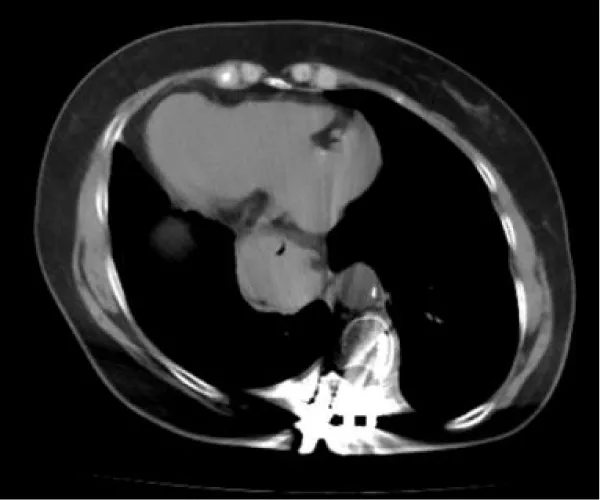

The patient had a history of spinal correction surgery for scoliosis five years ago, during which her SIT was identified. Our CT exam and gastrogram proved her history, with a hernia sac measuring 35*48 mm (Figures 2-4). All routine laboratory tests were within normal limits.

Download Image

Figure 4: Abdominal CT before surgery.